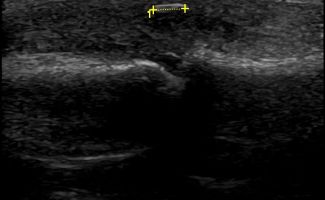

Tendon and Ligament Pathologies

- Tendonitis

- De Quervain's Tenosynovitis

- Rheumatological Tenosynovitis